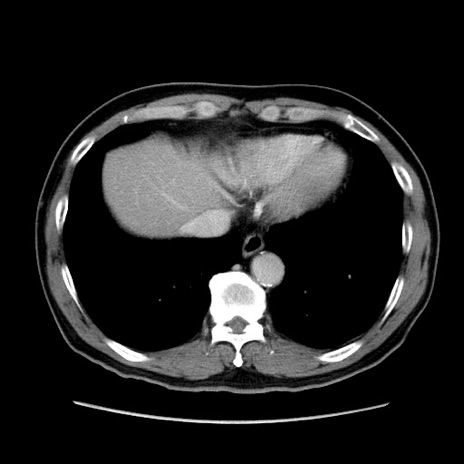

症例34(横断像)

【症例】60歳代 男性

【主訴】右鼠径部膨隆

【現病歴】1年程前より右鼠径部膨隆あり。自己にて還納可能だったため放置していた。3時間前より右鼠径部の脱出を認め、還納困難となり受診。

【既往歴】高血圧

【身体所見】右鼠径部に小児頭大の膨隆あり。弾性硬であり、用手還納は困難。左鼠径部にも膨隆を認める。脱出はなし。

【データ】WBC 15500、CRP 測定なし